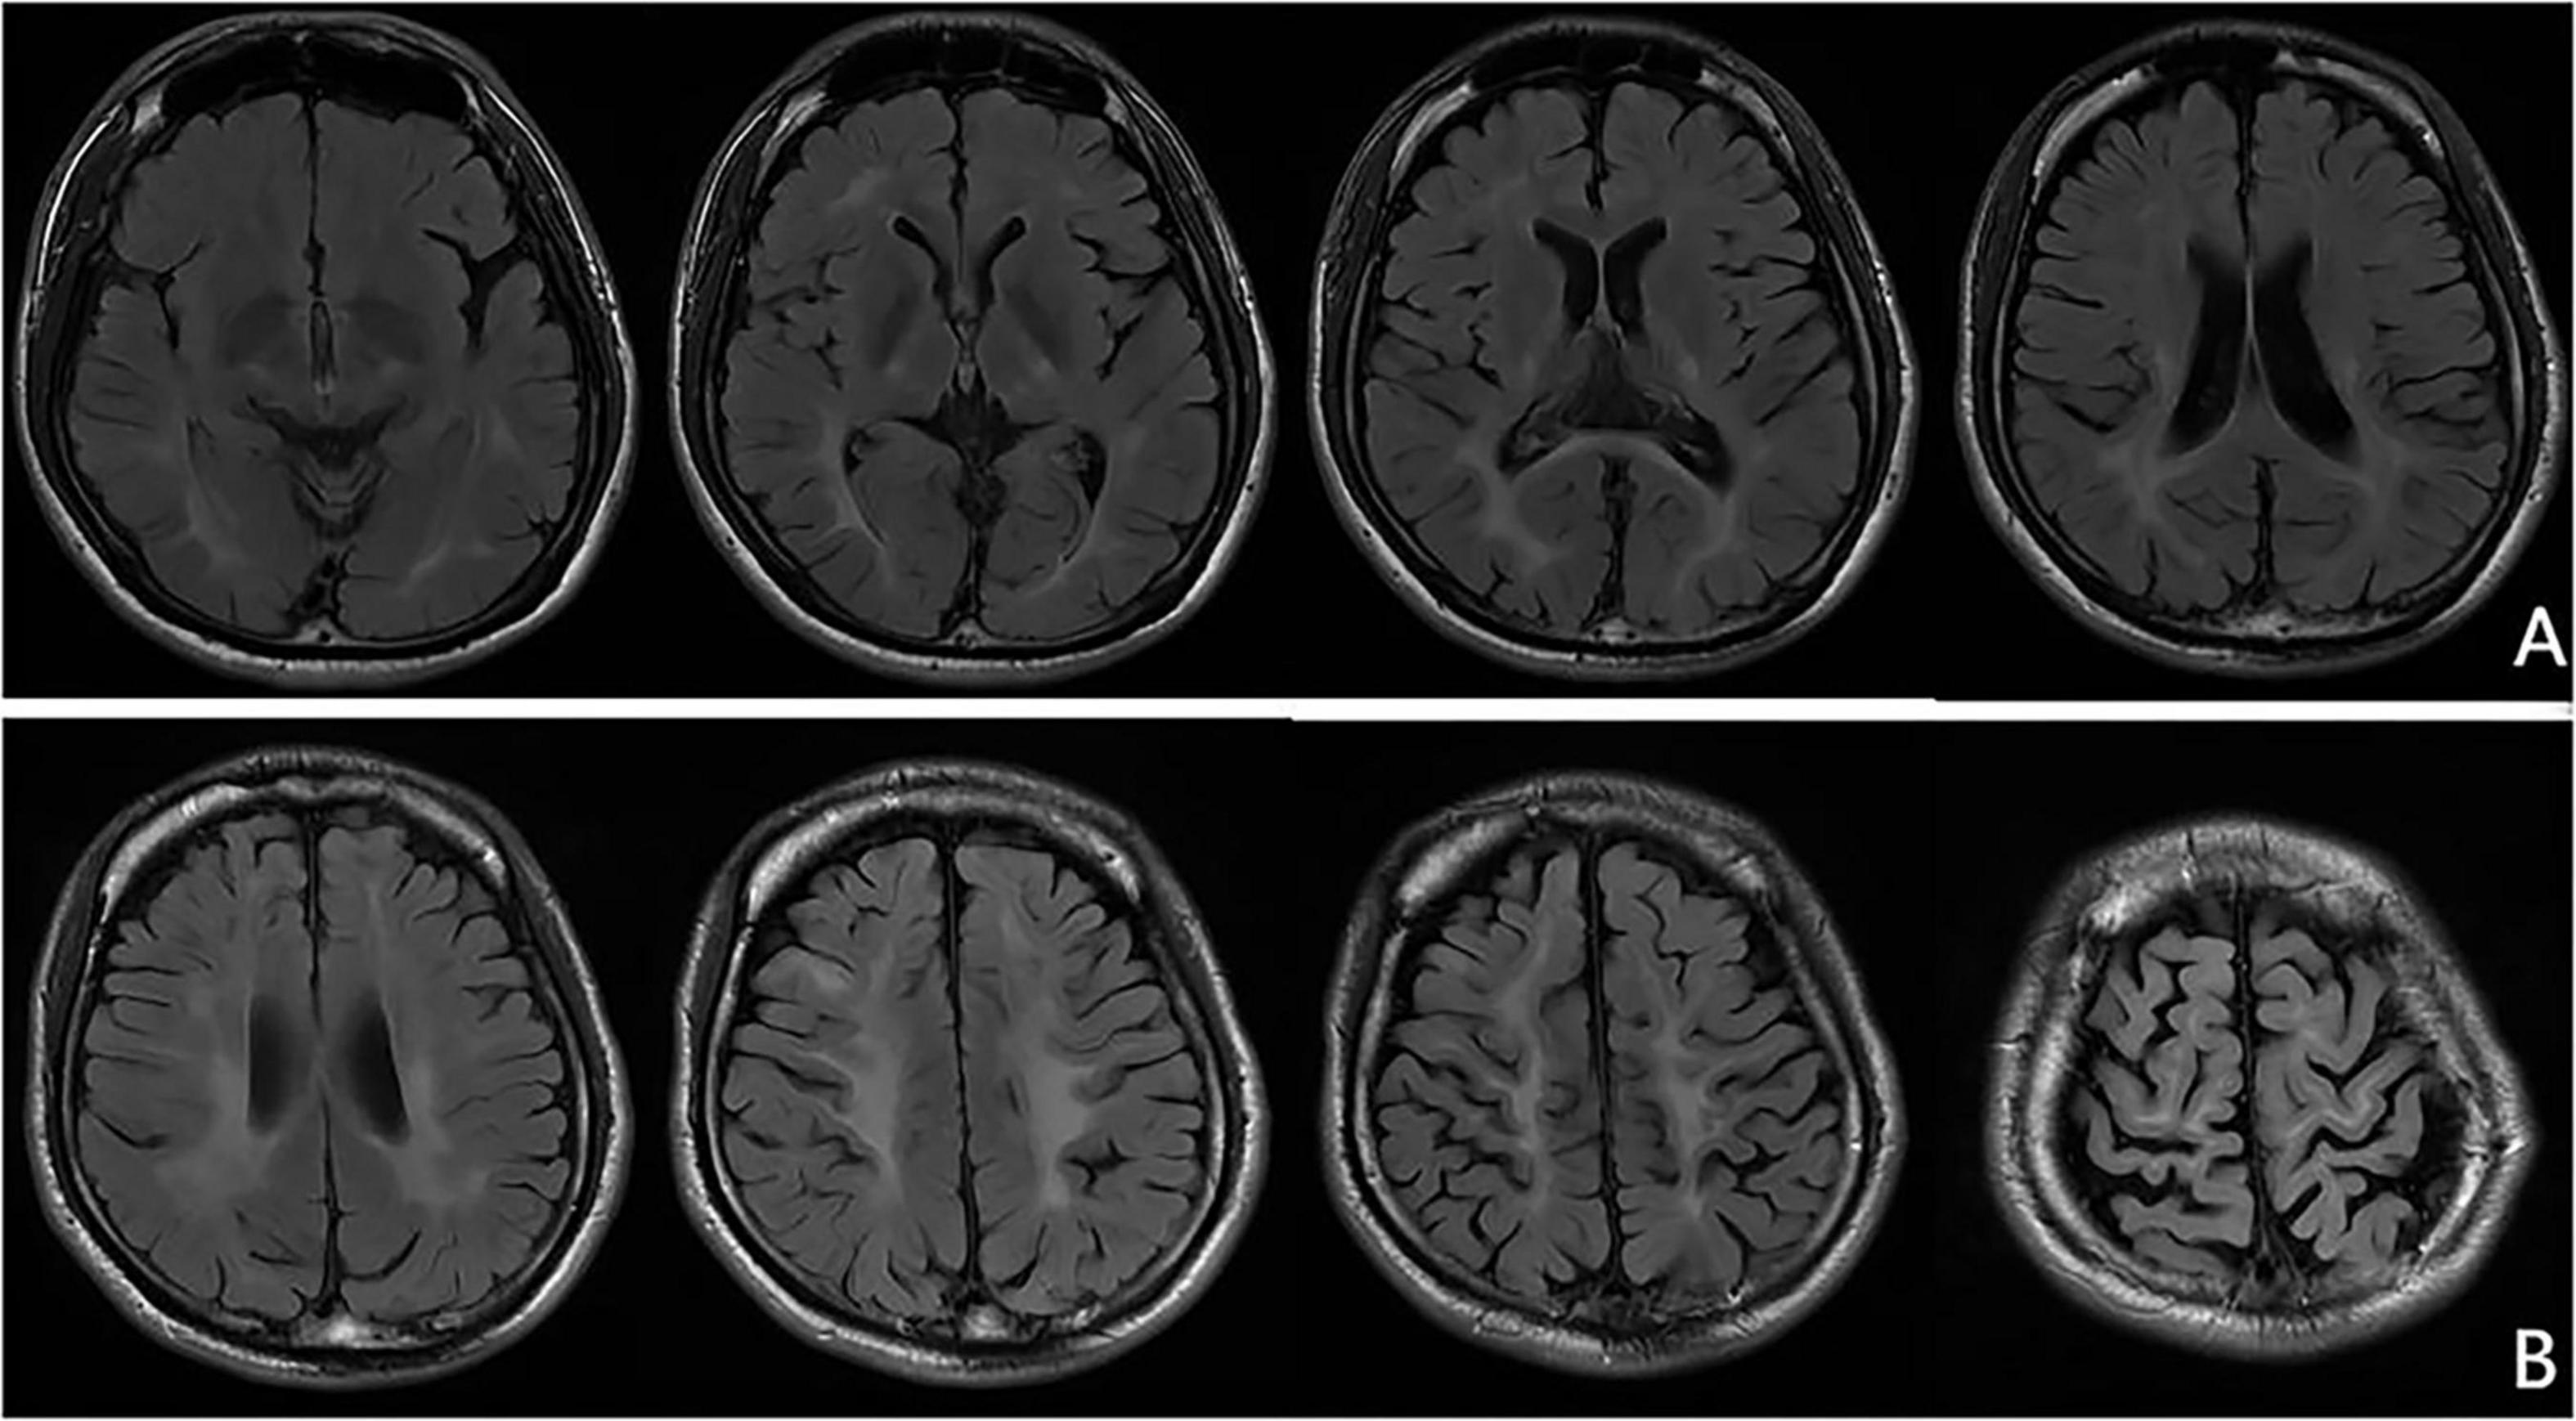

At the age of 16 years, his brain MRI showed bilateral high-signal abnormalities in the periventricular white matter and corticospinal tracts, along with a lesion in the right frontal subcortical region (Figure 2A). And the age of 26 detected symmetrical lesions in the bilateral corticospinal tracts, optic radiations, splenium of the corpus callosum, bilateral corona radiata, and the centrum semiovale (pre- and postcentral gyri) white matter, along with newly observed diffuse cerebral atrophy (Figure 2B). Subsequent MRIs conducted in 28 years old demonstrated progressive involvement of the frontal, parietal, temporal, and occipital lobes (Figures 3A–H). Physical examination revealed pes cavus (high-arched feet). While the patient denied marked sensory deficits, the neuroelectrophysiological examination revealed peripheral nerve damage, mainly demyelinating changes, and bilateral abnormal upper and lower limb sensory evoked potentials (Figure 4). So far, he has not exhibited significant visual decline. Ophthalmologic evaluation at Zhongshan Ophthalmic Center confirmed corrected visual acuity of 1.0 bilaterally, normal visual fields on perimetry, and unremarkable fundus examination, excluding optic nerve involvement. Cognitive assessment using the Mini-Mental State Examination (MMSE) yielded a score of 28/30 (adjusted for junior high education level), indicating preserved cognitive function. Laboratory test results were normal, including the amino acid and acylcarnitine spectrum analysis, content of very long chain fatty acids, adrenocorticotrophic hormone, cortisol, and creatine kinase.

FIGURE 2

MRI brain scans organized in two rows labeled A and B. Row A displays four images of transverse sections showing symmetrical brain tissue patterns with visible ventricles. Row B contains five scans, showing different levels of the brain with distinctive sulci and gyri patterns. All images highlight the cerebral structures in grayscale.

Figure 2. Representative brain MRI at the ages of 16 and 26 years (T2 FLAIR, coronal planes). (A) Brain MRI at the age of 16 detected symmetrical hyperintensities in the bilateral periventricular white matter and bilateral corticospinal tracts, as well as patchy hyperintensity in the right frontal subcortical region. (B) Brain MRI at the age of 26 detected symmetrical lesions in the bilateral corticospinal tracts, optic radiations, splenium of the corpus callosum, bilateral corona radiata, and the centrum semiovale (pre- and postcentral gyri) white matter, along with newly observed diffuse cerebral atrophy.

Neuroimaging of KD typically shows symmetrical lesions in the periventricular white matter, corticospinal tracts, and optic radiations (Cousyn et al., 2019; Muthusamy et al., 2019). In the patient of this study, MRI revealed not only characteristic white matter abnormalities but also initial right frontal subcortical signal abnormalities, progressing to involve bilateral fronto-parietal cortex and cortical atrophy as the disease developed. Notably, Ketata et al. described parieto-occipital lesions in KD, linking to psychosine-mediated demyelination and neuroinflammation (Ketata and Ellouz, 2024). The fronto-subcortical findings of this study may share similar pathogenesis, reflecting regional vulnerability to psychosine toxicity. It is possible that KD had a broader spectrum of radiological patterns, underscoring the need for further studies to clarify its pathophysiology, clinical significance, and potential prognostic implications.